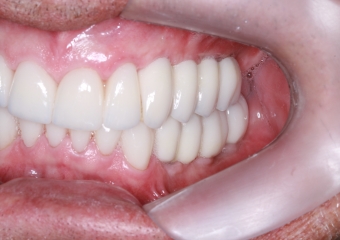

Intra oral direita final

Intra oral esquerda final